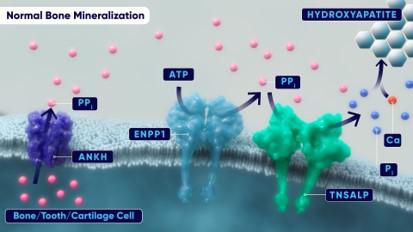

In July 2019, we formed a joint venture with Exscientia Limited ("Exscientia"), an Oxford, UK-based artificial intelligence ("AI") and machine learning drug discovery company with a proprietary chemical design platform to discover novel small molecule drug candidates. Exscientia was acquired by Recursion Pharmaceuticals, Inc. ("Recursion") in 2024 and we have continued work with Recursion on the discovery of a small molecule targeting an Ectonucleotide Pyrophosphatase/ Phosphodiesterase 1 ("ENPP1") inhibitor for the treatment of HPP. HPP is a rare, genetic disease characterized by mutations in the ALPL gene. The ALPL gene provides instructions for making an enzyme called tissue-nonspecific alkaline phosphatase, which plays an important role in the growth and development of bones and teeth. The incidence of HPP has been reported to be 1 in 100,000 to 1 in 300,000 (United States and Canada) for severe disease and 1 in 6,370 (European Union) for less severe forms. These mutations lead to diminished activity of the alkaline phosphatase enzyme and the accumulation of inorganic pyrophosphate (“PPi”), which inhibits bone mineralization causing multiple skeletal pathologies. We believe that a small molecule inhibitor of ENPP1 has the potential to bring meaningful benefit to HPP patients by reducing excess levels of pyrophosphate, thereby removing an inhibitor of calcium mineralization and bone formation.

In 2024 we presented data at the American Society for Bone and Mineral Research ("ASBMR") from an early lead ENPP1 inhibitor, REV101, in a mouse model of later-onset HPP demonstrating a 30% reduction in PPi, a key biomarker that is elevated in HPP and contributes to poor bone mineralization. Together with Recursion, we also advanced REV102, an ENPP1 inhibitor for the treatment of patients with HPP to position the molecule for additional preclinical development activities in 2025.